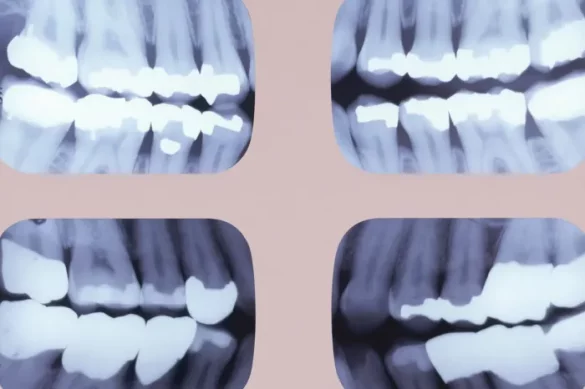

Bitewing radiography is a way used to seize snap shots of the crowns of your posterior enamel, specially your premolars and molars. The name “bitewing” comes from the unique method wherein sufferers bit down on a small wing or tab connected to the movie withinside the mouth. Modern bitewing strategies on the whole use holders with plastic systems and virtual sensors, making the technique extra snug and snap shots clearer.

This x-ray is specially designed to recognition at the regions wherein cavities are maximum probable to develop: among the returned enamel. The bitewing is specific amongst dental x-rays as it isn’t supposed to expose the enamel roots or the place close to the top of the roots, however instead it is supposed to offer an in depth go phase of the top and decrease enamel wherein they contact every different.

A conventional bitewing x-ray targets to in reality display the crowns of each top and decrease premolars and molars. The fundamental intention is to seize the regions wherein those returned enamel contact, due to the fact those touch factors are enormously vulnerable to decay and are regularly invisible at some point of a preferred visible exam.

In maximum dental practices, a hard and fast of 4 bitewing x-rays is taken— on every facet of the mouth. The standard insurance includes:

- Premolars (additionally called bicuspids): First and 2nd premolars are a first-rate recognition due to the fact those are transitional enamel among the dog (the “eye enamel”) and primary molar.

- Molars: First and 2nd molars are crucial for checking decay and current restorations like fillings and crowns. If a 3rd molar (expertise enamel) is gift, its inclusion relies upon on its alignment and relevance to the patient’s oral health.

- The bitewing have to normally begin simply distal (behind) to the dog enamel, preferably catching the distal fringe of the dog as a landmark. The photo then extends all of the manner to the returned of the arch, overlaying to the final gift molar, that’s regularly the second one or 1/3 molar for the patient.